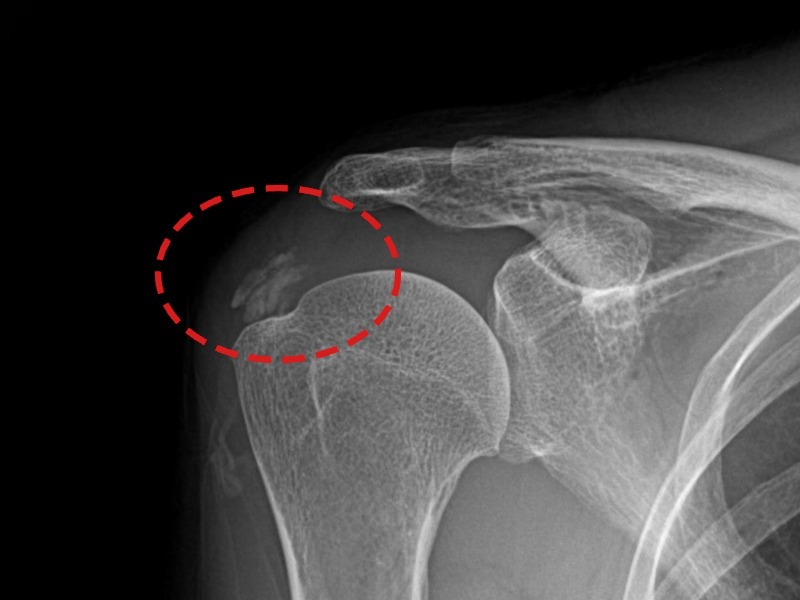

[촬영시기:21.09.02~21.10.07]

[석회분쇄흡입술] 좌측 어깨 통증으로 팔을 옆으로 올리기 어려워진 60대 남성 환자로, X-ray에서 좌측 극상근건 내 석회 침착이 확인되어 석회분쇄흡입술을 시행하였습니다.